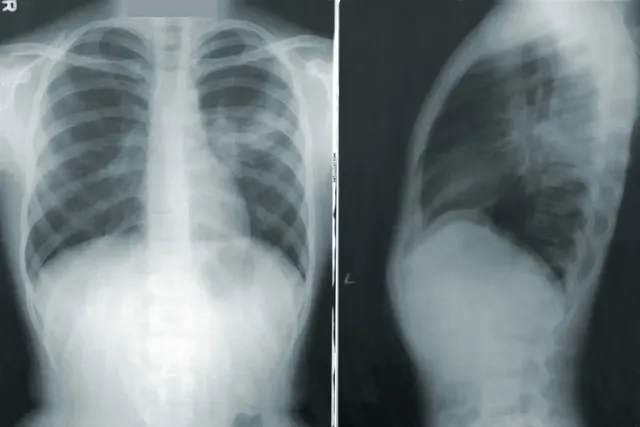

2. 척추 측만증

많은 사람들이 알고 있으면서 방치하고 있는 대표적인 척추 측만증이 있습니다. 일상 생활에서 크게 불편함을 못 느끼고 있고 대부분 사람들이 그냥 방치하는 경우가 많습니다.

척추 측만증이 있으신 분들은 평소 자세가 매우 중요하며 척추가 옆으로 휘어져 있기 때문에 등이 아픈 이유, 즉 등 통증의 원인이 되기 때문에 오른쪽이나 왼쪽으로 기울어져 있으면 한쪽으로 통증이 발생할 수 있습니다.